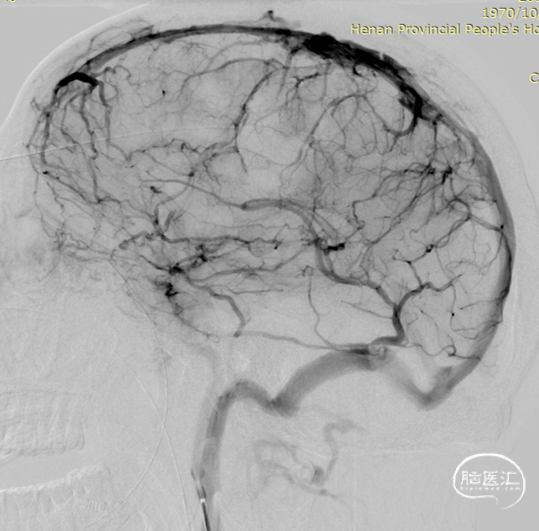

术后造影显示上矢状窦较前明显改善。

术后上矢状窦再通